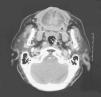

Acta Otorrinolaringológica Española Arteria carótida interna paralela a la base del cráneo

Arteria carótida interna paralela a la base del cráneo

Internal carotid artery parallel to the skull base